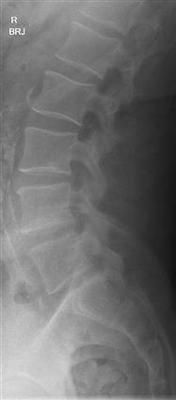

Radiographer X-ray Findings:

Findings

As requested, a spot lateral and a lateral view have been performed.

There appears to be a very minor anterolisthesis of L5 relative to S1 in the order of only 2-3mm and degenerative.

There is no other malalignment.

There is no fracture.

There is no destructive pathology.

There is good preservation of intervertebral disc heights.

There certainly is a mild anterolysthesis at L5 but this is unlikely to cause front of the thigh pain. Is your knee feeling weak on stairs? Has the quadriceps reflex been tested? Normal? With pinprick is there any difference right and left?